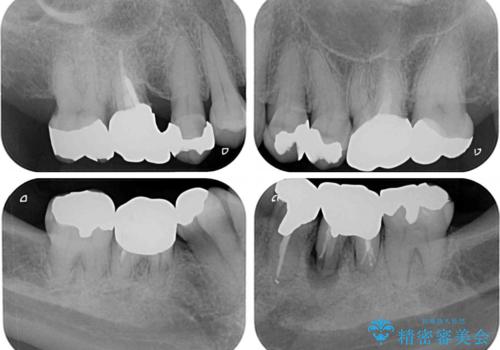

- 口腔内にある銀歯を全て外したいとのことで来院された患者様です。

土台に含まれている金属も含め、口腔内の金属は全て除去し、抜歯しなければならない歯は抜歯し、オールセラミッククラウンやセラミックインレーにて治療することとしました。

上下奥歯の抜歯を同時期に行わず、下顎の治療を終えてから上顎を抜歯して治療を進めたため、1年ほどの期間を要しました。